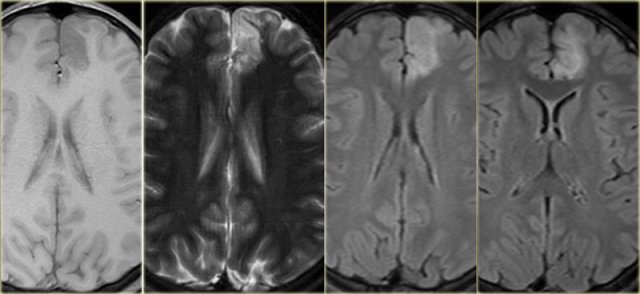

T1WI

Superior for cortical thickness and the interface between grey and white matter.

On T1WI look for grey matter occuring in an aberrant location as in gray matter heterotopia.

FLAIR

Look very carefully for cortical and subcortical hyperintensities on the FLAIR, which can be very subtle.

Since FLAIR may show false-positive results due to artefacts, the abnormalities should be confirmed on T2WI.

T2* or SWI

Helpful when searching for haemoglobin breakdown products as in posttraumatic changes and cavernomas, or to look for calcifications in tuberous sclerosis, Sturge-Weber, cavernomas and gangliogliomas.